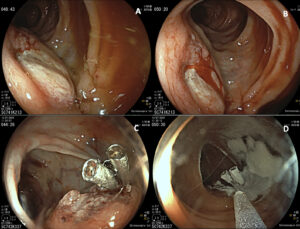

A 74-year-old male with previous history of diverticulosis presented to the emergency department for the third time in a month with complaints of hematochezia. Patient reported a 10kg weight loss in the past month. Blood test results revealed hemoglobin 11.7g/dL. Colonoscopy showed an elevated 30mm lesion with central mucosal disruption and active bleeding, located at the splenic flexure of the colon (Fig 1A-B). Endoscopic hemostasis was achieved with diluted adrenaline, through-the-scope clips, and hemostatic powder (Fig 1C-D). Biopsies were performed but inconclusive. CT angiography revealed a 7.5 x 5.5 cm lobulated, exophytic lesion with peripheral enhancement and central hypodense areas, extending from the transverse colon and in direct contact with the pancreatic tail (Fig2). This also showed perilesional adenopathies and multiple liver metastases.

Figure 1 : Colonoscopy images. A and B: Elevated lesion with central mucosal disruption and active bleeding, located at the splenic flexure of the colon; C and D: Endoscopic hemostasis was achieved with diluted adrenaline, through-the-scope clips, and hemostatic powder.